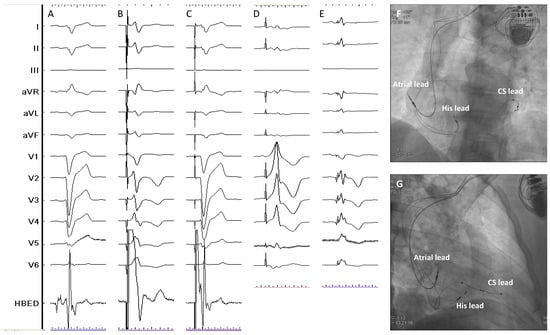

- Vijayaraman, P.; Herweg, B.; Ellenbogen, K.A.; Gajek, J. His-Optimized Cardiac Resynchronization Therapy to Maximize Electrical Resynchronization: A Feasibility Study. Circ. Arrhythm. Electrophysiol. 2019, 12, e006934. [Google Scholar] [CrossRef]

- Zweerink, A.; Zubarev, S.; Bakelants, E.; Potyagaylo, D.; Stettler, C.; Chmelevsky, M.; Lozeron, E.D.; Hachulla, A.L.; Vallée, J.P.; Burri, H. His-Optimized Cardiac Resynchronization Therapy with Ventricular Fusion Pacing for Electrical Resynchronization in Heart Failure. JACC Clin. Electrophysiol. 2021, 7, 881–892. [Google Scholar] [CrossRef] [PubMed]